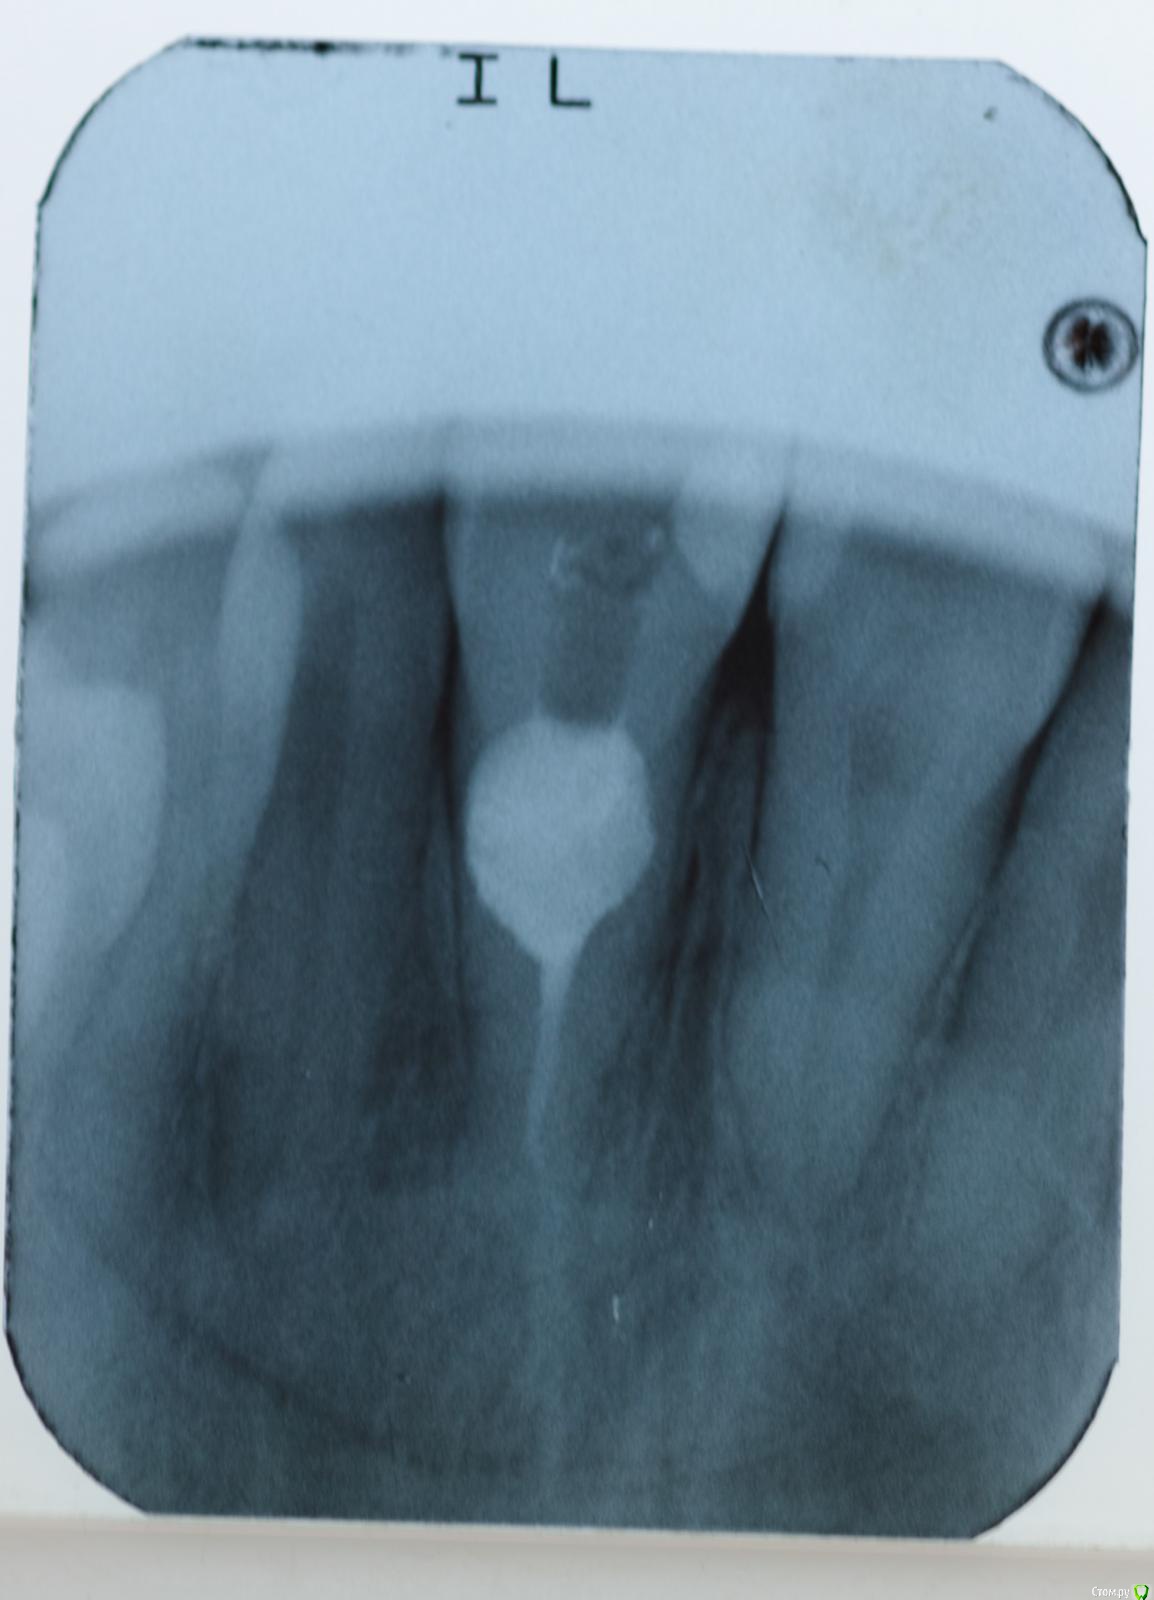

skeettrap Опубликовано 5 апреля, 2016 Поделиться Опубликовано 5 апреля, 2016 Случай двухлетней давности. Коллега привела подругу. Жалобы только на свищ в области данного зуба с грануляциями. Делали на "сколько простоит". Сегодня попросил администратора вызвать пациентку для контроля. Если придет, то будет продолжение. 1 Ссылка на комментарий

skeettrap Опубликовано 5 апреля, 2016 Автор Поделиться Опубликовано 5 апреля, 2016 (изменено) Латеральная конденсация. В очаге резорбции - МТА. Изменено 5 апреля, 2016 пользователем skeettrap Ссылка на комментарий